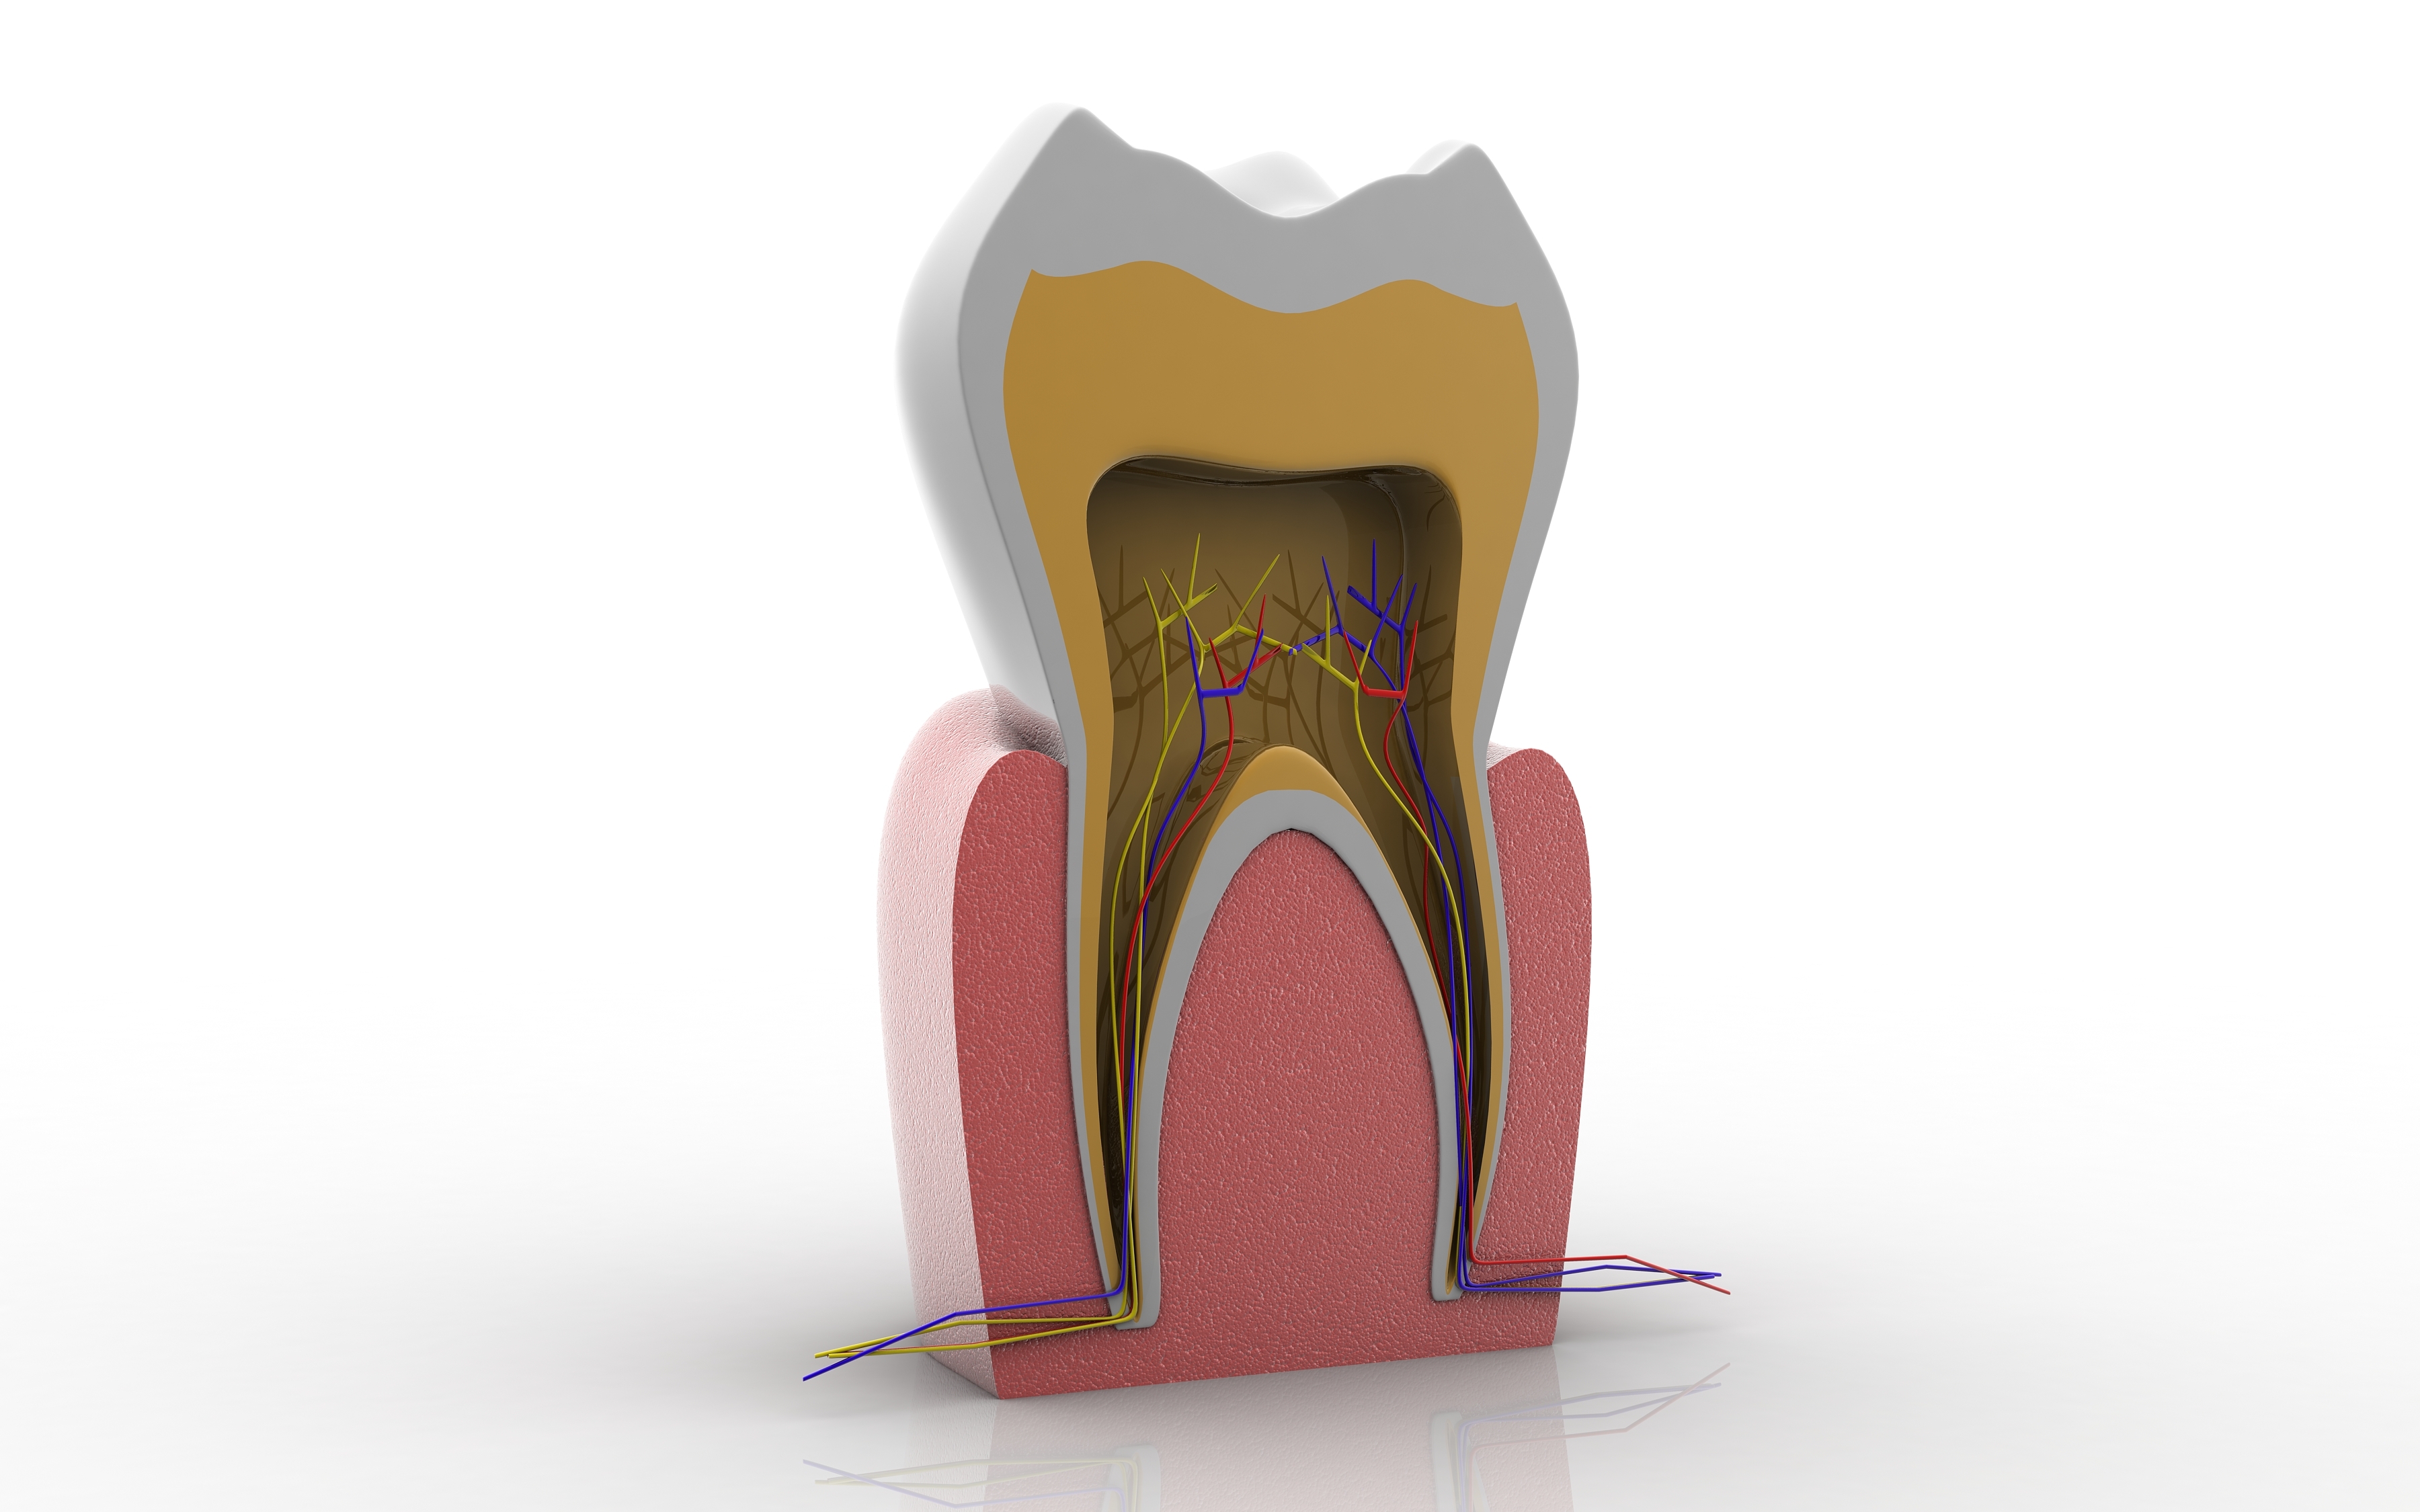

Dott.ssa ERIKA BARBALONGA PIEZOSURGERY in oralchirurgie und direkten IMPLANTOLOGIE Mit der Anwendungstechnik Piezosurgery fuehrt man Eingriffe in Oralchirurgie alls (Aufbau der Kiefernhole, Innenknochen Zystektomie, Wurzelspitzenresktion, komplizierte Extraktionen, Implantatrvorbereitung...) um Traumas zu verhindern und mit Genmanipulazion des Knochens fuer eine rapide Heilung. Ausserdem ist die Verwendung sehr innovativ und effizient fur die Implantatechnik und Knocheregeneration, die uns erlauben Rehabilitazion fur Prothetikpazienten und Steigerung der Stabilitaet der mobilen Prothetik. Mit der direkten Belastung, fixe Zaehne innerhalb in 24 h! Mit geringer invasiven Behandlung und ohne Stress, dank der chirurgischen Piezosurgery - Technik und der Sedierung (Beruhigungsmittel/Narkose) Führen Oralchirurgie mit minimal-invasiven Techniken : - Komplexe Zahnextraktionen ( verlagerte Zähne , überzählige Zähne dysodontiasis ) - Entfernung von Zysten , - Endodontische Chirurgie ( Wurzelspitzenresektion ) - Parodontalchirurgie (Zahnfleisch-Aufklappung , Knoch- und Schleimhauttransplantate ) . - Sinuslift FRUEHERKENNUNG VON MUNDKREBS Unser Engagment in der Foerderung der Kultur der oralen Gesundheit und Praevention im allegemeinen weiterhin hochaktuell, speziell die onkologische Praevention stellt eine der Saeulen unseres Geschaefts. Die fruehzeitige Erkennung von Veraenderungen der Mundschleimhaut erhoehen erheblich die Ueberlebenschancen im Falle von Krebs der Mundhoehle. Fruherkennung bedeutet Gewebeveraenderungen zu entdecken, bevor sie mit blassen Augen sichtbar werden. Die Loesung kommt von Gewebe - Fuoreszenz, die sie tief orale Schleimhautver - aenderungen sehen kann. Mit der speziellen Technologie koennen eine vorbeugende Diagnose untersuchen Bauteilqualitaet orale Schleimhaeute und verwalten werden. BEWUSSTE SEDIERUNG Eine effektive und effiziente Behandlung basiert in der Lage auf, in einer "ruhigen" - Situazion zu behandeln, und dies gilt fuer den Erwachsenen und den kleinen Pazienten. Angst haben, die eine zahnaerztliche Behandlung unterziehen muessen, kann unnoetige Schwierigkeiten fuer den Anwender und Pazienten erstellen. Bewusste Sedierung, mit Nasalmasken oder Intravenoes durch einen Fachmann in Anaesthesiologie, stellt eine therapeutische Waffe an, auf die sie sich verlassen koennen, um diese Themen, sowie eine Reihe von anderen Hilfsmitteln zur Entsspannung des Pazienten zu beheben.

• CONSERVATIVA ED ENDODONZIA